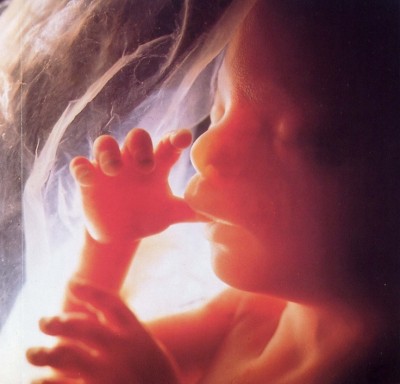

Végére a trimeszterében, a baba növekszik, akár 20 cm-es, és aktívan vizsgálja az univerzum, míg az anya méhében van korlátozva neki. És hat hónap, a gyermek lehet lenyelni, mosoly, ásít, és még sírni, amikor az édesanyja dohányzik, iszik, vagy eszik valamit, ami nem tetszik neki.

Utoljára harmadik trimeszterében - időtartamra finomítására. Fordulnak elő az utolsó pillanatokban a magzat, az utolsó simításokat, hogy a megjelenése egy kis remekmű.

Csillók, a szemöldök, a haj a fejen nyilvánvaló. Frizuráink lagúna. hogy a korábban bevont baba leesik. Bár számos közülük maradhat a váll, hát, még a születéskor. Jó esélye van a túlélésre születéskor pedig csak a 32. hét, amikor is a szövetek és szervek alakulnak teljesen csak a fény még mindig kell érlelni, így koraszülött csecsemők gyakran igényelnek eszköz szellőztető. Szintén 32. hét a gyermek az összes reflexek szükséges születéskor, ezek több mint 70, köztük szopás, mohó, taposógép.

Miután 36 hét a terhesség, a baba elkezd hízni gyorsan. Az anyja méhében egyre zsúfolt. A bőre kisimul, rózsaszín, elveszti ráncos megjelenést. Villog, akkor a reakció a fény. Az idegrendszer, az agy fejlődik minden nap. Gyermek a 38-40 héten készen a születése teljesen tüdeje érett és készen áll, hogy lélegezni légköri levegőt. Ő megváltoztatja a pozícióját, felkészülés a megjelenése a mi világunkban.